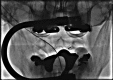

Pathologic fractures involving the C2 vertebral body and odontoid process pose a unique dilemma, as the surgical approach for direct odontoid process screw fixation has several limitations. There have been a small number of transoral approach C2 vertebroplasty or kyphoplasty reported in the literature. Previous attempts were performed utilizing fluoroscopy or CT guidance. We report a case of a fluoroscopically guided transor-al approach vertebroplasty in a patient with a lytic lesion involving the C2 vertebral body, extending into the odontoid process with an underlying pathologic fracture. This case is unique as two separate punctures were required in order to adequately stabilize the pathologic fracture, CTA was performed preoperatively to better evaluate regional vasculature, and a post-procedure rotational flat panel CT was performed to assess cement placement.